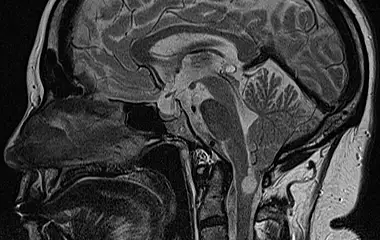

Der Bereich Hydrozephalus, Chiari-Malformation und Tethered-Cord-Syndrom umfasst die Diagnostik und Behandlung komplexer Erkrankungen des Liquorsystems sowie des Gehirns und Rückenmarks. Wir behandeln angeborene und erworbene Formen des Hydrozephalus, einschließlich des Normaldruckhydrozephalus, der sich häufig durch Gangstörungen, kognitive Veränderungen und Blasenfunktionsstörungen äußert. Ein weiterer Schwerpunkt ist die Chiari-Malformation, bei der es zu einer Verlagerung von Kleinhirnanteilen in den Spinalkanal kommen kann und die vielfältige neurologische Symptome verursachen kann. Das Tethered-Cord-Syndrom beschreibt eine krankhafte Fixierung des Rückenmarks, die sowohl in klassischer als auch in okkulter Form auftreten und zu Schmerzen, neurologischen Defiziten oder Funktionsstörungen führen kann. Ziel unserer Behandlung ist es, neuralen Strukturen zu entlasten, eine weitere Schädigung zu verhindern und die Lebensqualität der Patientinnen und Patienten zu verbessern. Grundlage hierfür sind eine präzise Diagnostik, individuell abgestimmte Therapiekonzepte und eine umfassende, verständliche Aufklärung.

Bei Hydrozephalus bieten wir verschiedene Formen der Liquorableitung an, darunter den Liquorshunt und den ventrikuloperitonealen Shunt (VP-Shunt), individuell angepasst an die jeweilige Erkrankung. Als alternative, shuntunabhängige Therapie führen wir die endoskopische Drittventrikulozisternostomie (ETV) durch, sofern die anatomischen Voraussetzungen gegeben sind. Patientinnen und Patienten mit Arnold-Chiari-Malformation behandeln wir durch eine gezielte mikrochirurgische Dekompression, um den Liquorfluss zu verbessern und neurologische Symptome zu lindern. Beim Tethered-Cord-Syndrom, einschließlich okkulter Formen, setzen wir auf ein minimalinvasives Detethering zur schonenden Entlastung des Rückenmarks.